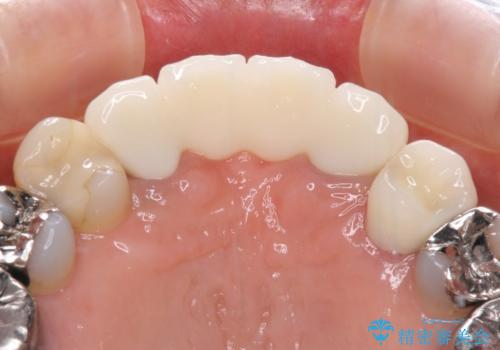

仮歯自体はとても綺麗でしたが、2本の歯が欠損している部分に上唇小帯が入り込んでいたため、歯肉形成を行った上で仮歯を調整し、オールセラミックブリッジを装着することとしました。

上唇小帯を切除したことで、ブリッジのダミー部分に触れて腫れていた歯肉は健全な状態になりました。

隙間もなくなったことで話す際の空気の漏れや、ものが挟まることもなくなりました。